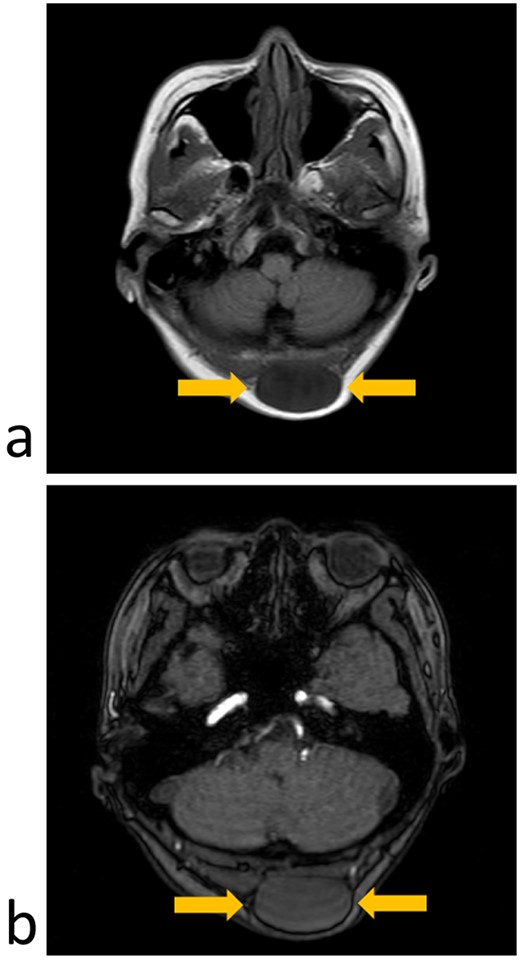

Magnetic resonance imaging (MRI) of her head revealed a discrete, well-defined tumor in the compartment of the left occiput. The internal structure of the tumor was heterogeneous and showed a low-intensity signal on T1-weighted images and an isointense signal on T2-weighted images (Fig. 2). The clinical diagnosis was an SCL or lymphangioma.

MRI imaging (axial section); (a) T1-weighted image showing a low-intensity signal area under the scalp; (b) T2-weighted images showing an isointense signal of the tumor.